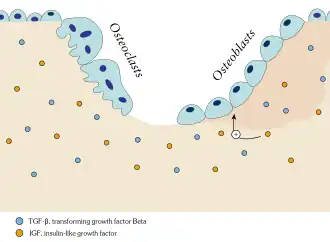

Subsequent to appropriate signaling, osteoclasts move to resorb the surface of the bone, followed by deposition of bone by osteoblasts. Together, the cells that are responsible for bone remodeling are known as the basic multicellular unit (BMU), and the temporal duration (i.e. lifespan) of the BMU is referred to as the bone remodeling period.[7]

Osteoblasts actively synthesizing osteoid containing two osteocytes..jpg) Illustration showing bone remodelling cycle